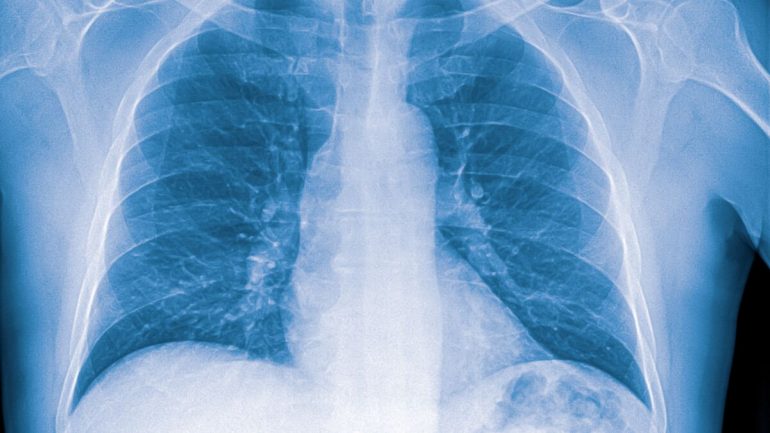

Silicose : une pathologie qui peut entrainer l’invalidité et la mort

386 000 décès par an, c’est le bilan des maladies provoquées par l’exposition à la poussière selon un rapport de l’Organisation Mondiale de la Santé depuis 2022. Parmi ces maladies on retrouve notamment la silicose, qui peut être aiguë, chronique ou accélérée. Qu’est-ce c’est que la silicose et quelles sont ses causes ? Oriane Hounkpè, Médecin généraliste nous donne des explications.